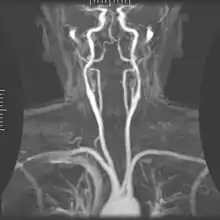

The posterior cerebral artery (PCA) is one of a pair of arteries that supply oxygenated blood to the occipital lobe, part of the back of the human brain. The two arteries originate from the distal end of the basilar artery, where it bifurcates into the left and right posterior cerebral arteries. These anastomose with the middle cerebral arteries and internal carotid arteries via the posterior communicating arteries.

![]() The arterial circle and arteries of the brain. The posterior cerebral arteries (bottom forks) arise from the basilar artery (center). | |